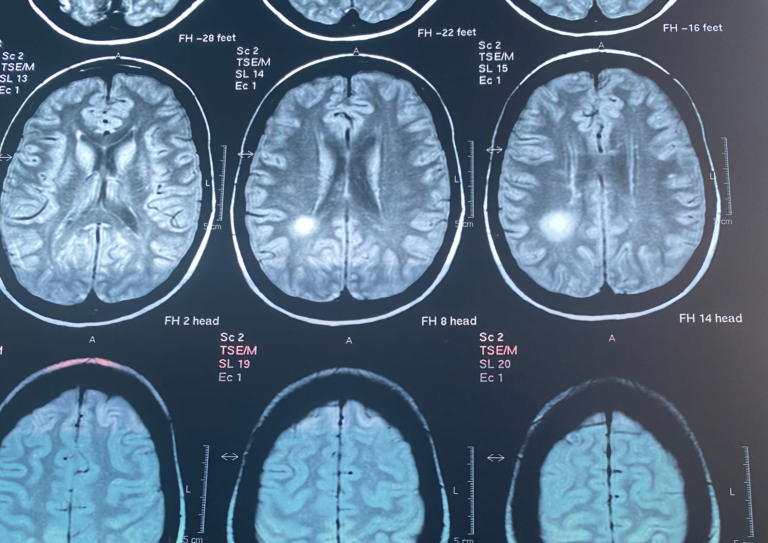

The neurologist at the time thought to start already with some medication even before my official diagnosis. The very first treatment that I had was some cortisone pills for about five months. I had done already multiple MRI’s that have shown many lesions, especially one lesion that was really, really big. I also had my results of the spinal tap. I just got a confirmation that «Yes, yes indeed, you have M.S.» and this is all I knew.

In an MRI that I did four years ago in the middle of my treatment with Gilenya, it showed a small improvement in my overall results of that MRI. So this was really wonderful. During that time, I was not just taking my treatment and relying only on that. I was also doing a lot of breathing exercises and also I had some sessions with a coach that helped me with a field called Neuro Athletics that is basically focusing on helping the body and different parts of the body to wake up again and to work in a better way. And this was especially in my feet because I didn’t feel my feet. I still don’t feel them 100 %. But let’s say the left especially was very bad.